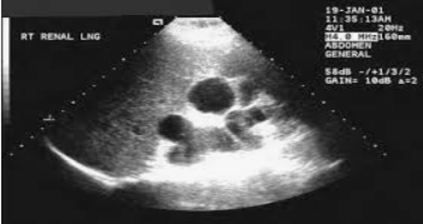

A urinary tract infection (UTI) is an infection of some part of your body's urinary system, which includes your:<br />• Kidneys<br />• Ureters (tubes that carries urine from your kidneys to your bladder)<br />• Bladder<br />• Urethra (a short tube that carries urine from your bladder to outside your body)<br />Bacteria cause most UTIs. Anyone can get one, but they're most common in women, and they can be extra concerning if you're pregnant. If you think you might have a UTI, tell your doctor. With proper care, you and your baby should be fine.<br />Usually, these infections in the bladder and urethra. But sometimes they can lead to kidney infections. If they do, UTIs may lead to preterm labor (giving birth too early) and low birth weight.<br />UTI Symptoms…<br />If you have a UTI, you may have:<br />• An urgent need to pee, or peeing more often<br />• Trouble with peeing<br />• A burning sensation or cramps in your lower back or lower belly<br />• A burning feeling when you pee<br />• Urine that looks cloudy or has an odor<br />• Blood in your pee, which can turn it red, bright pink, or cola-colored,<br />If you have a kidney infection, you may have:<br /> <br />• Fever<br />• Nausea<br />• Vomiting<br />• Upper back pain, often on just one side<br />If you have symptoms of a kidney infection, see your doctor right away. Without treatment, the infection can spread into your bloodstream and cause life-threatening conditions.<br />Why Are UTIs More Common During Pregnancy?<br />Hormones are one reason. In pregnancy, they cause changes in the urinary tract, and that makes women more likely to get infections. Changes in hormones can also lead to vesicoureteral reflux, a condition in which your pee flows back up from your bladder to your kidneys. This can cause UTIs.<br />When you’re pregnant, your pee has more sugar, protein, and hormones in it. These changes also put you at higher risk for a UTI. Because you’re pregnant, your growing uterus presses on your bladder. That makes it hard for you to let out all the urine in your bladder. Leftover urine can be a source of infection.<br />Other causes of UTIs include:<br />• Escherichia coli and other bacteria from your poop. E. Coli is the most common cause of UTIs and can move from your rectum to your urethra if you don’t wipe from front to back.<br />• Sexual activity. Fingers, your partner’s penis, or devices can move bacteria near your vagina into your urethra.<br />• Group B streptococcus. Many women have this bacteria in their colon and vagina. It can cause UTIs and women can pass it to their newborns. Your doctor will test you for this bacteria around weeks 36 to 37 of pregnancy. If you’re positive for group B strep, your doctor will give you IV antibiotics during labor.<br />UTI Diagnosis…<br />You’ll take a urine test. Your doctor will test it for bacteria and red and white blood cells. A urine culture may also be checked. It shows what kind of bacteria are in the urine.<br />UTI Treatment During Pregnancy…<br />You’ll take antibiotics for 3 to 7 days or as your doctor recommends. If your infection makes you feel uncomfortable, your doctor will probably start your treatment before you get your urine test results.<br />Your symptoms should go away in 3 days. Take all of your medication on schedule anyway. Don’t stop it early, even if your symptoms fade.<br />Many common antibiotics -- amoxicillin, erythromycin, and penicillin, for example -- are considered safe for pregnant women. Your doctor wouldn’t prescribe others, such as ciprofloxacin (Cipro), sulfamethoxazole, tetracycline, or trimethoprim (Primsol, Proloprim, Trimpex), that can affect your baby’s development.<br />UTI Complications During Pregnancy<br />Pyelonephritis is a UTI that affects the kidneys. If you’re pregnant it can cause:<br />• Preterm labor<br />• Severe infection<br />• Adult respiratory distress syndrome<br />• Anemia<br />• Long-term infection<br /><br /><br />UTI Prevention…<br /> <br />To try to avoid getting a UTI:<br />• Drink at least eight glasses of water a day.<br />• Wipe yourself from front to back when you go to the bathroom.<br />• Empty your bladder shortly before and after sex.<br />• If you need a lubricant when you have sex, choose a water-based one.<br />• Don't douche.<br />• Avoid strong feminine deodorants or soaps that cause irritation.<br />• Wash your genital area with warm water before sex.<br />• Wear cotton underwear.<br />• Take showers instead of baths.<br />• Don’t wear pants that are too tight.<br />• Pee often.<br />• Avoid alcohol, citrus juices, spicy food, and caffeinated drinks, which can irritate your bladder.<br /><br /><br />Dr. Bashar Hadi Alaaraji